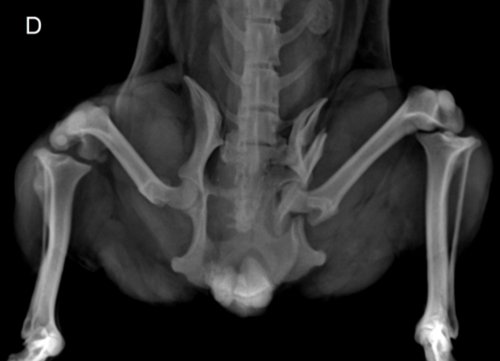

A clínica onde o Amendoim se encontra deu a ele uma nova chance e colocou o pequeno para adoção. Eu me ofereci para ajuda-lo e dar a vida que ele sempre mereceu. Porém, ele sofreu uma fratura bilateral na pelve com deslocamento e precisa de cirurgia para voltar a andar sem dor.